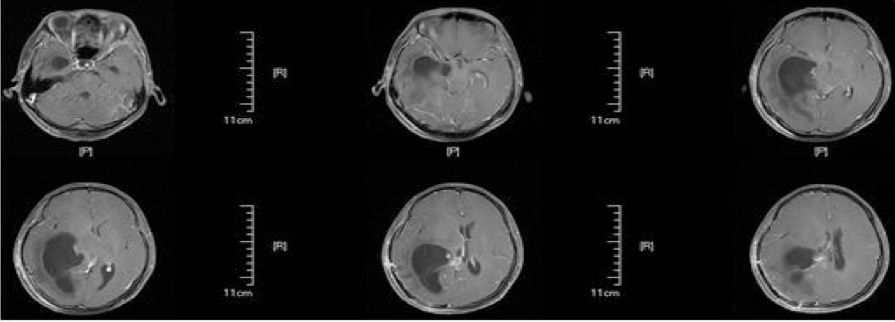

患者于术后第64天再次入院,入院后行头部MRI(图4)检查提示右侧侧脑室颞角、后角扩张并周围脑组织水肿、中线明显移位,并行腰穿测压为280cmH2O,诊断为右侧侧脑室三角区脑膜瘤切除术后孤立颞角综合征,遂于术后第68天行侧脑室颞角腹腔分流术,分流管为美敦力可调压力分流管,术中设定压力范围为105~125mmH2O,术后复查头部CT以及MRI(图5、6)。

图4. 磁共振检查提示右侧侧脑室颞角、后角扩张并周围脑组织水肿、中线明显移位。

图5. 显示V-P分流术后复查头部CT。

图6.显示V-P分流术后复查头部MRI。